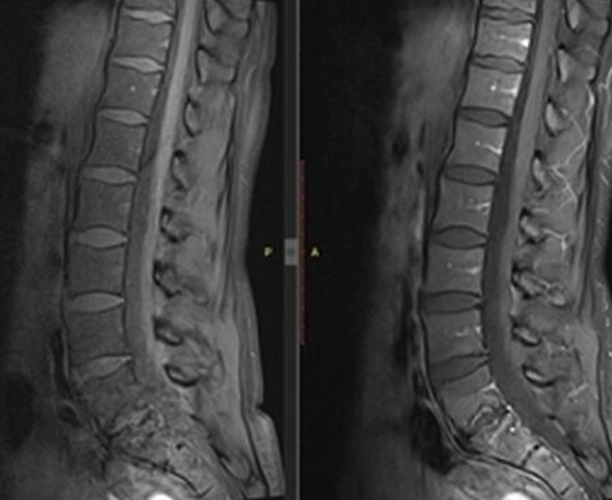

İncelemeler: Laboratuvar: AFR normal. Rutin biyokimya normal. Brucella negatif. HLA-B27 negatif. Görüntüleme: Sakroiliyak MR olağan. Mevcut lomber MR’da L5–S1 düzeyinde spondilodiskit açısından şüpheli görünüm izlenmesi üzerine kontrastlı lomber MR istendi.

Kemik sintigrafisi görüldükten sonra spondilodiskit olasılığı elendi. L5-S1'deki disk lezyonu geçirilmiş bir travma ya da Schmorl nodülüne sekonder olarak artmış yoğun dejeneratif değişiklikler olarak değerlendirildi. 1600 mg/gün NSAİİ tedavisi ile kısmi fayda görüldü. Ağrı sadece sol değil sağ kasık bölgesine de ara ara yayılım gösteriyor artık ancak şiddet daha azdı. Hastaya fizyoterapi, günlük yaşam aktivitelerinde dikkat etmesi gerekenler ve kısıtlamalar önerildi ve takip planlandı.